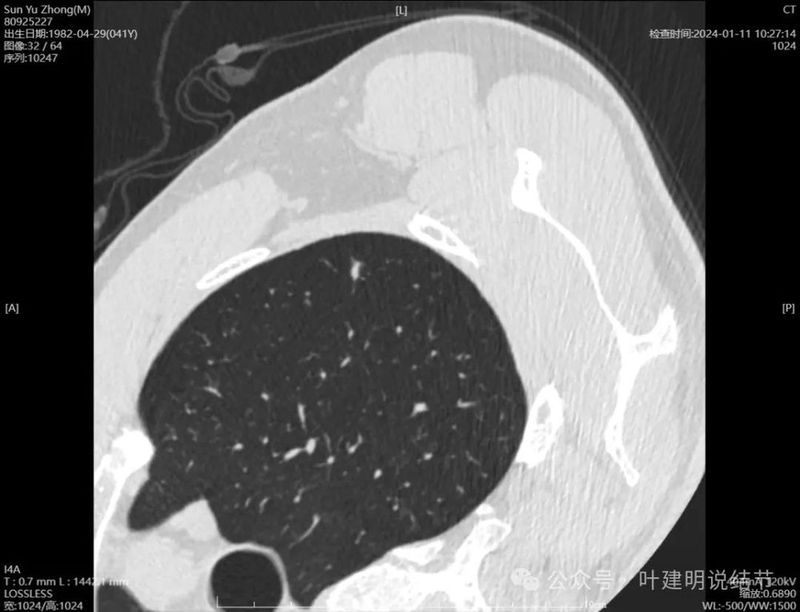

右侧病灶连续层面:

病灶出现,密度较淡。

轮廓清楚,血管贴边,也有血管弯征,瘤肺边界清楚。

轮廓与边界清,没有明显实性成分。

中间的密度稍低于周围部位。

轮廓清楚,边缘不光滑。

边缘区较淡。